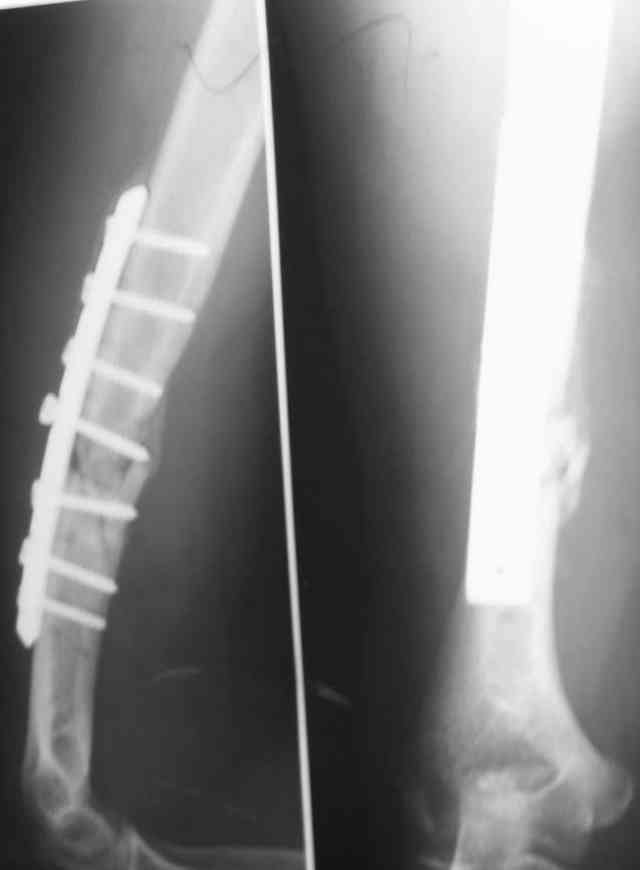

Уважаемые коллеги! Помогите в выборе тактики лечения больной Р.,56 лет, с болтающимся ложным суставом с/3 правой плечевой кости 2-х летней давности. В анамнезе - бронхиальная астма, гормонозависимая форма, ожирение III cт. Травма - автодорожная, получила закрытый многооскольчатый перелом диафиза плечевой кости со смещением (от метафиза до метафиза), в экстренном порядке нами произведен закрытый остеосинтез стержневым аппаратом, отломки удалось сопоставить анатомически. В дальнейшем больная выпала из поля зрения. Как потом выяснилось, после снятия стержневого аппарата, больная долечивалась по Илизарову специалистом из г. Кургана. Аппарат Илизарова удален из-за нагноения мягких тканей. Последние два года работая бухгалтером, фиксирует плечо ортезом. Теперь вновь обратилась к нам для ликвидации ложного сустава.

Есть вариант открытого вмешательства с резекцией зоны ложного сустава, костной пластикой и накостным остеосинтезом хорошей пластиной, в смысле мощной и длинной.

>A.Ch< Есть вариант открытого вмешательства с резекцией зоны ложного сустава, костной пластикой и накостным остеосинтезом хорошей пластиной, в смысле мощной и длинной.

Вряд ли для больной с ожирением и астмой большая травматичная операция с большим риском вослеоперационной нейропатии лучевого нерва является лучшим выходом...

Мы бы предложили БИОС ретроградно (хотя это не принципиально, можно и сверху). Учитывая,что ложняк "болтающияся", больших трудностей с закрытым вскрытием канала (в зоне ложного сустава) быть не должно. Конечно нужен инструмент: сначала длинная (350-400 мм) острая спица (шило)диаметром 4-5 мм., затем гибкие развертки до 8-9 мм и соответствующий массивный штифт...

У нас в клинике было два подобных случая. Один пациент до обращения к нам перенес девять хирургических вмешательств в разных медучреждениях города.

Штифт - отвисание проксимального отдела - накостный остеосинтез, нагноение, АФВ с ревизиями раны, опять пластина и снова нестабильность. Была удалена пластина и выполнен БИОС штифтом ChM (ДЕОСТ). Через 2 нед. пациент сел за руль и вышел на работу. Причем так и работает до сих пор уже 1,5 года, хотя полного сращения мы вроде бы не достигли ( снимки пришлю позже) - пациент не приходил на осмотры, общался только по телефону.

Второй пациент перенес два неудачных накостных остеосинтеза на фоне пареза лучевого нерва. Была удалена пластина и выполнен БИОС штифтом ChM (ДЕОСТ) - это была наша первая операция БИОС.